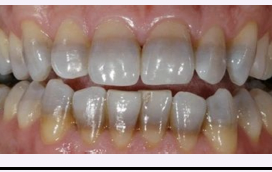

Tetracycline staining

● Tetracycline exposure during tooth mineralization binds to calcium ions, causing permanent tooth staining.

● Location and severity of the discoloration depend on the stage of tooth development at the time of

exposure.

● Staining typically appears as yellow, brown, or gray bands in affected teeth.

● Tetracycline is not recommended for children under age 8, as permanent tooth calcification is still

incomplete